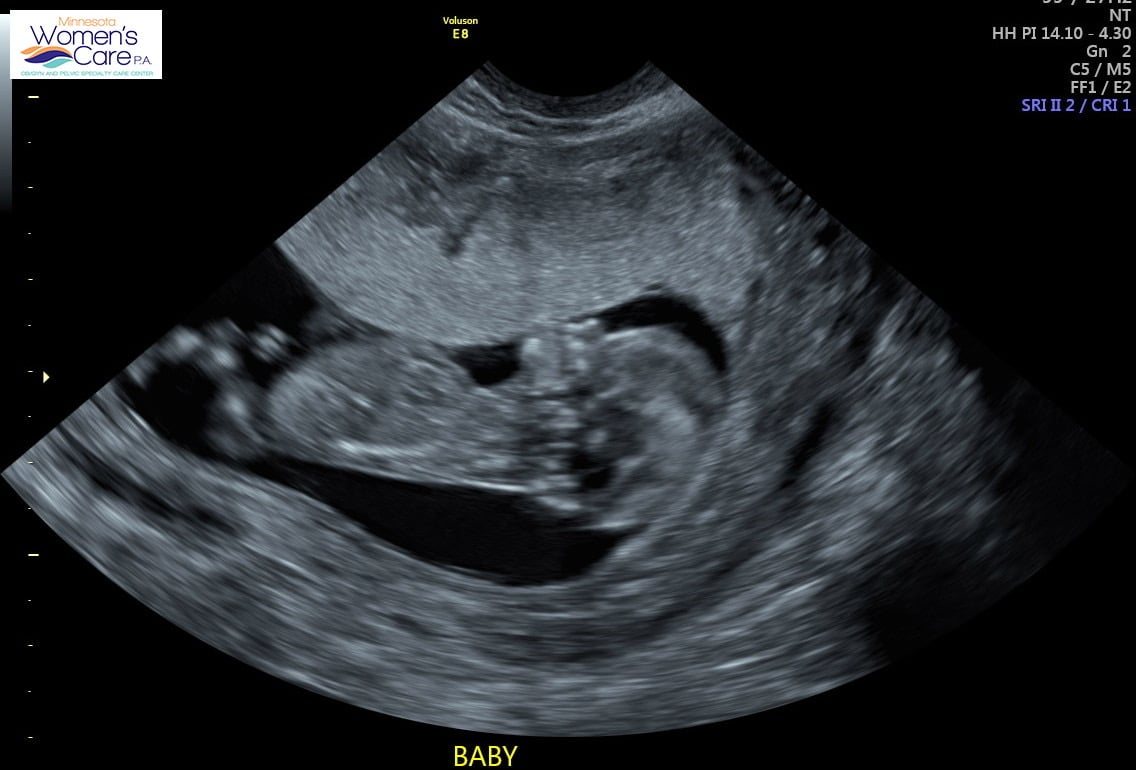

Crazy to see how big my uterus is in comparison lol.